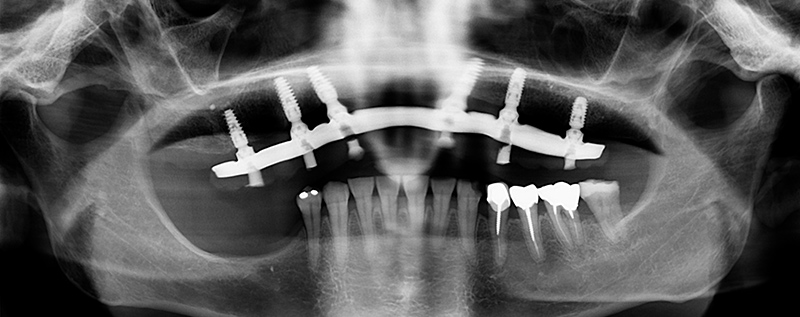

Fig. 01 : radiographie panoramique pré-opératoire.